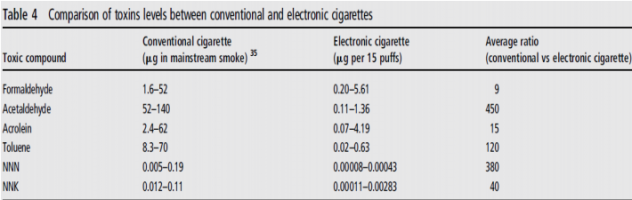

Если говорить о других токсичных веществах, таких как формальдегид, ацетальдегид и пр., то их содержание в электронных сигаретах (третий столбец) намного ниже, чем в обычных (второй столбец):